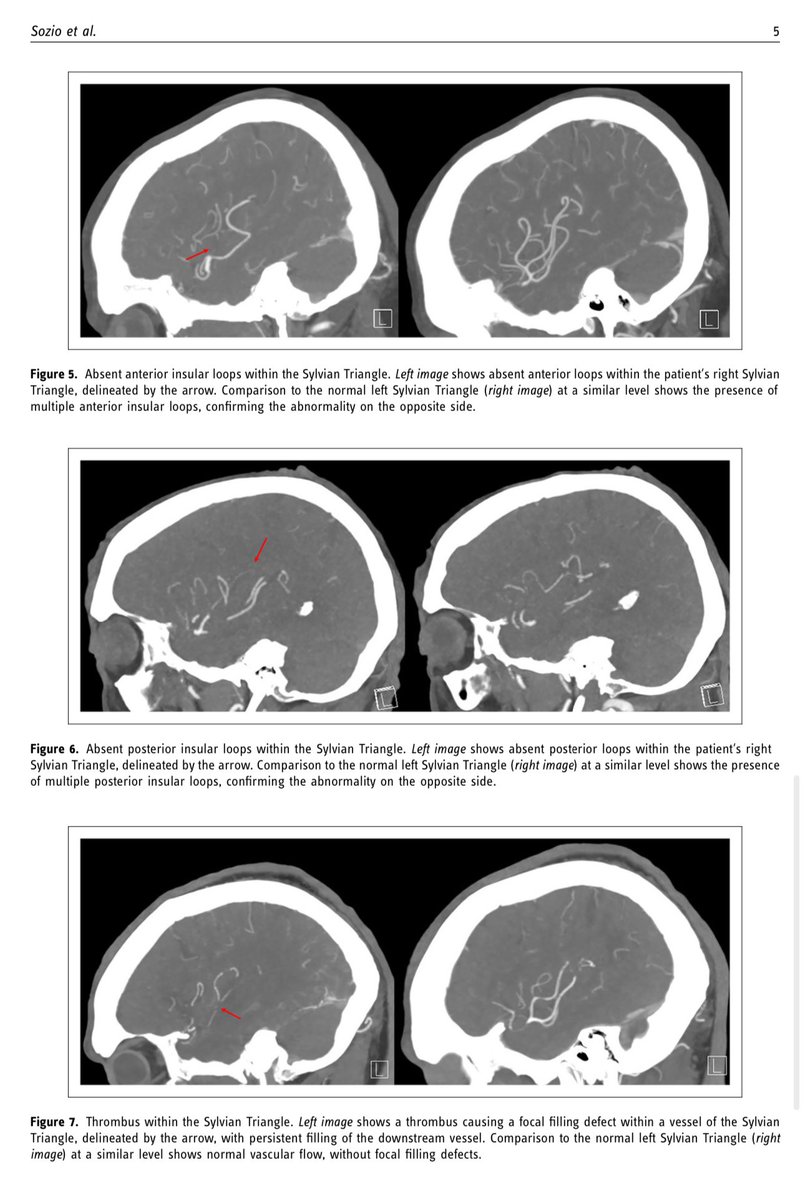

Honored to have our article on using sagittal CTA to identify the Sylvian triangle for M2,M3,M4 occlusions published (helps ID candidates for distal occlusion tx). Article dedicated to our NeuroIR mentor Dr. Irwin Keller who passed away last year. #neuroir #stroke #neuroradiology